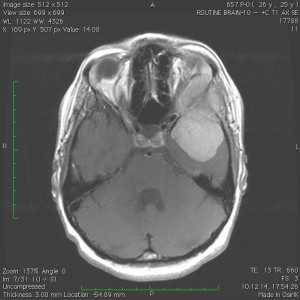

Пациентка В., 25 лет. В возрасте 9 лет перенесла острый лимфобластный лейкоз, по поводу чего проводилась лучевая терапия.

За 2 месяца до поступления в стационар появилась боль в левой височной области, левом глазном яблоке, слезотечение. Консультирована офтальмологом — выявлено высотные левого глазного яблока на 6 мм, по сравнению с правом глазным яблоком, а также признаки внутричерепной гипертензии в виде застойных дисков зрительных нервов. При МРТ выявлена больших размером внемозговая опухоль средней черепной ямки с гиперостозом и распространением в глазницу слева.